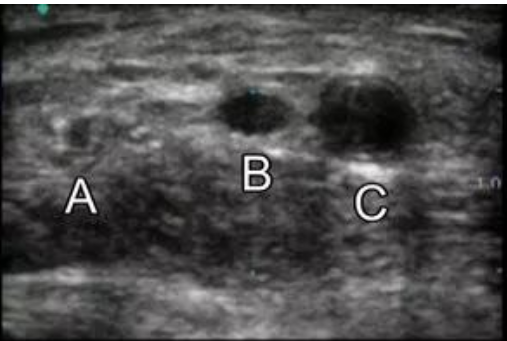

2.2 新建内瘘的成熟与穿刺点确认,运用超声技术可以更方便的了解内瘘成熟情况与可穿刺段血管的情况!

第二步,根据触诊和超声检查情况,为患者绘制AVF穿刺计划图,注明狭窄、禁穿刺区域、静脉保护区域等;也要借助超声技术。